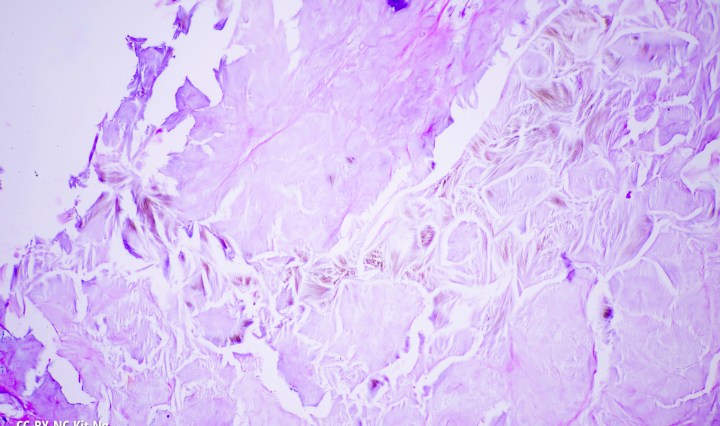

Gout Crystals in Human Skin

The gout crystals, formed from uric acid, can be seen under human skin in this specimen. Second field showing gout crystals from the same human specimen. (TM: 100x, picture taken with a Zeiss 10x Planapo on a Sony A7ii) Continue reading Gout Crystals in Human Skin